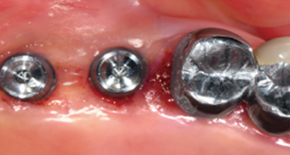

3. Bone graft

4. Placement of MagiCore